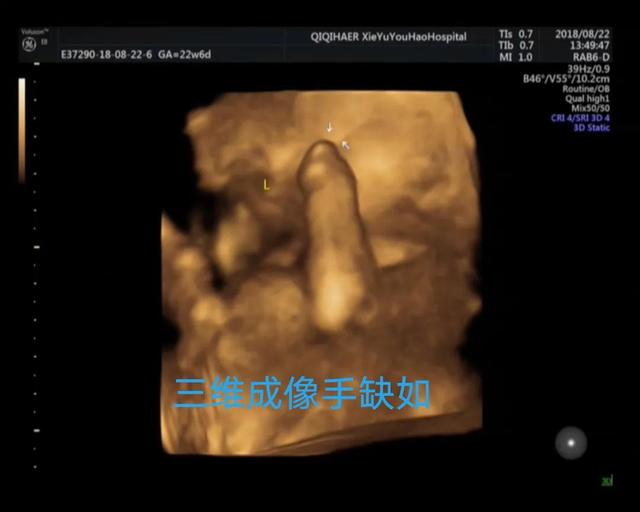

案例2

病例2、3、4清晰的三维成像让临床医生的指导更加精准,马宝和家人对诊断更加信服,也能及时做出下一步选择,将危害降到最低!